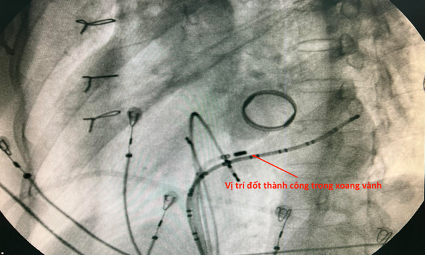

Tiến hành map vùng sau vách bên phải vòng van 3 lá ghi nhận điện thế nhĩ thất hoà vào nhau tương tự sau vách bên trái. Tiến hành cắt đốt vị trí này thì chấm dứt đường phụ nhưng sau đó tái phát lại. Tiến hành thăm dò vùng vị trí thượng mạc trong lỗ tĩnh mạch vành hướng về bên trái ghi nhận điện thế nhĩ thất hoà vào nhau làm 1, tiến hành cắt đốt vị trí này thì chấm dứt hoàn toàn đường dẫn truyền phụ này. Bệnh nhân khôi phục nhịp xoang dẫn truyền hoàn toàn qua nút nhĩ thất thông thường.

Hình: vị trí cắt đốt thành công trong xoang vành bằng catheter năng lượng cao và hình ảnh xoang vành.

Cắt đốt thành công mất sóng delta từ nhịp tim thứ 3, QRS hẹp lại.